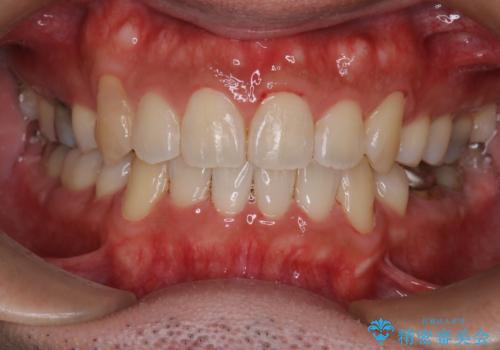

飛び出た八重歯!コンプレックスを払拭!

見た目、嚙み合わせ及び、治療期間や施術内容にご満足いただきました。